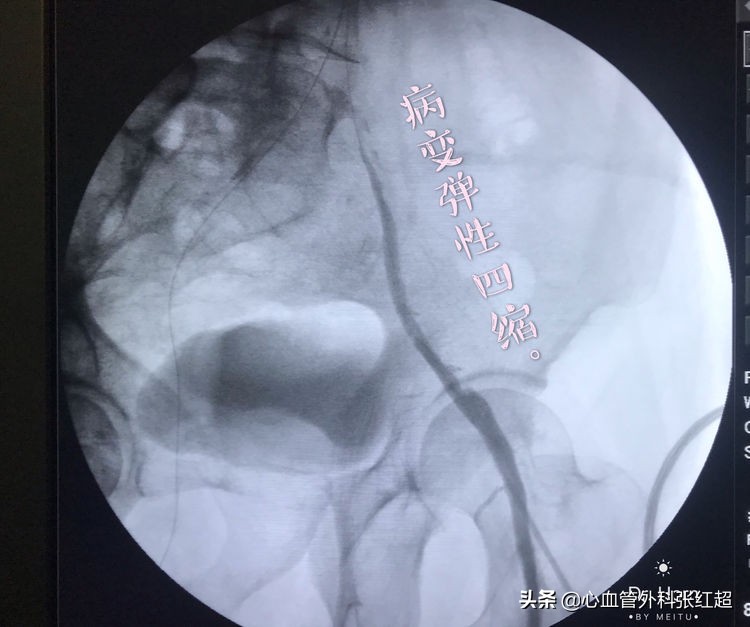

●LCIA闭塞全程闭塞病变

导丝进入假腔方向,加用微导管,换导丝破膜入真腔。

方位验证导丝入真腔后,用微导管造影进一步验证。